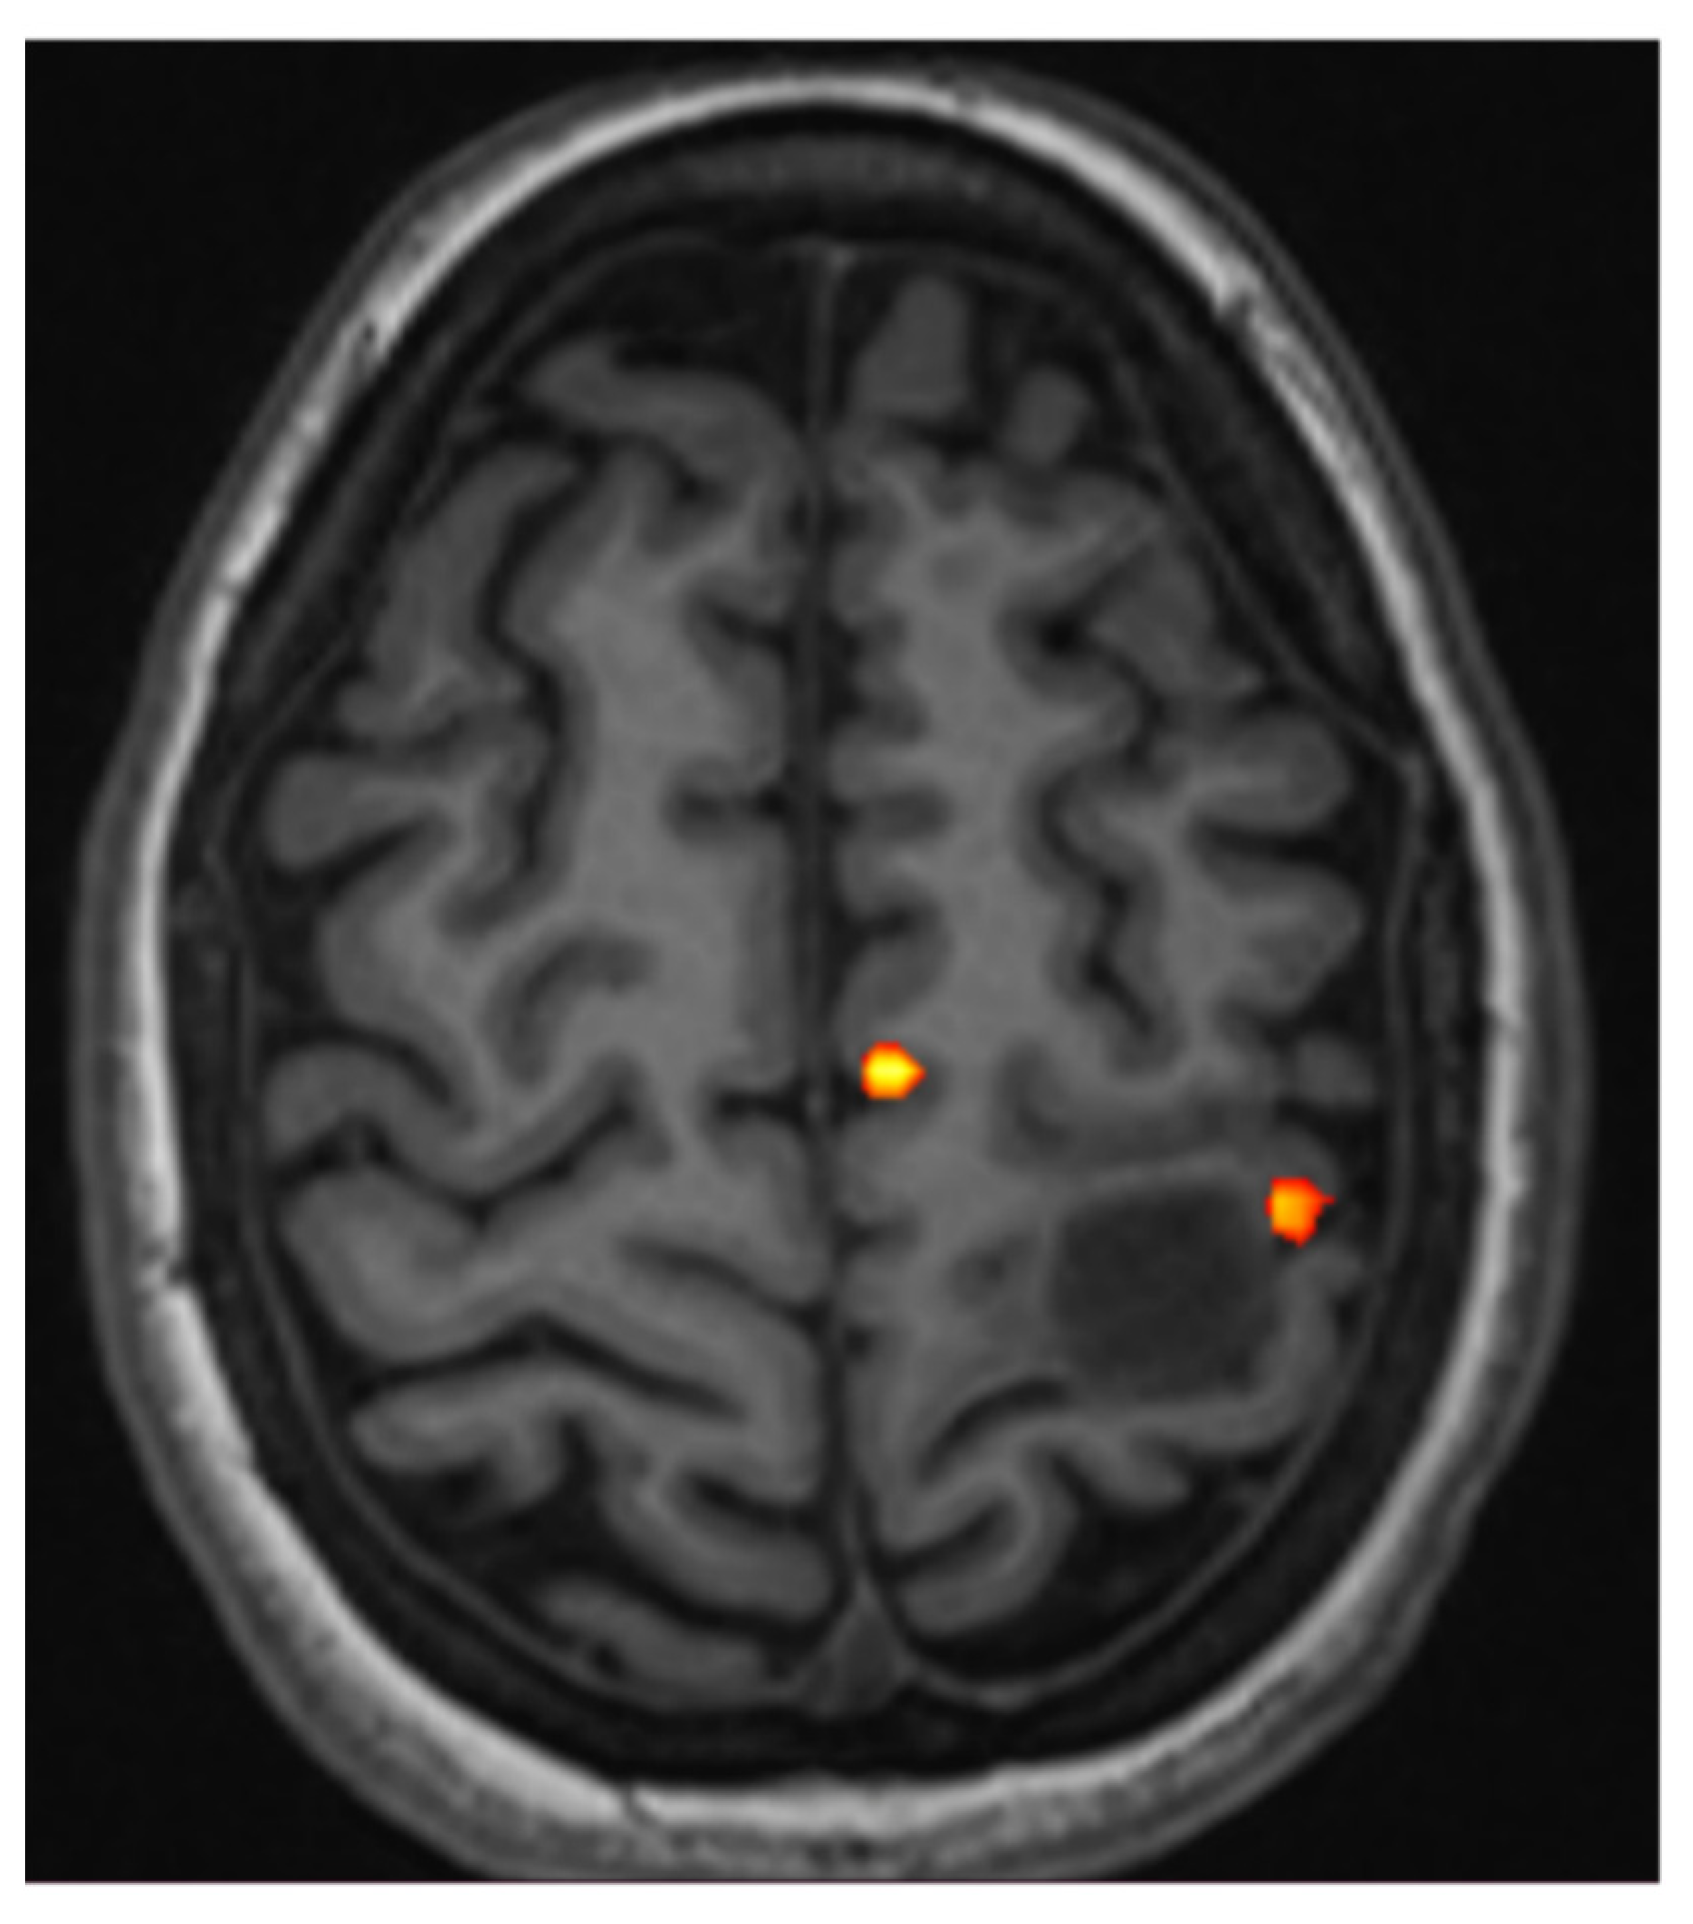

5.1. fMRI of Motor and Somatosensory Functions

- When the anatomy is effaced or partially effaced, and morphological Rolandic landmarks cannot be identified due to tumor growth;

- When a tumor lies in proximity to the identifiable motor hand area.